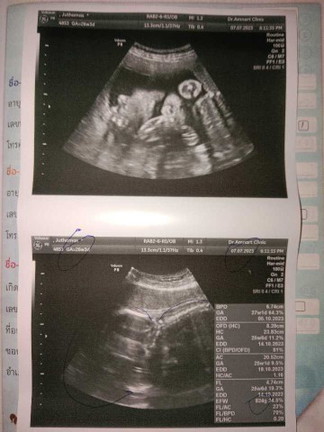

26w 3d ยังไม่ทราบเพศค่ะ

26 W 3 D น้ำหนักน้องอยู่ที่ 824g แม่ๆว่าน้ำหนักน้อยเกินไปมั้ยค่ะ #แม่ทางนี้แอบกังวลเรื่องน้ำหนักน้องค่ะ